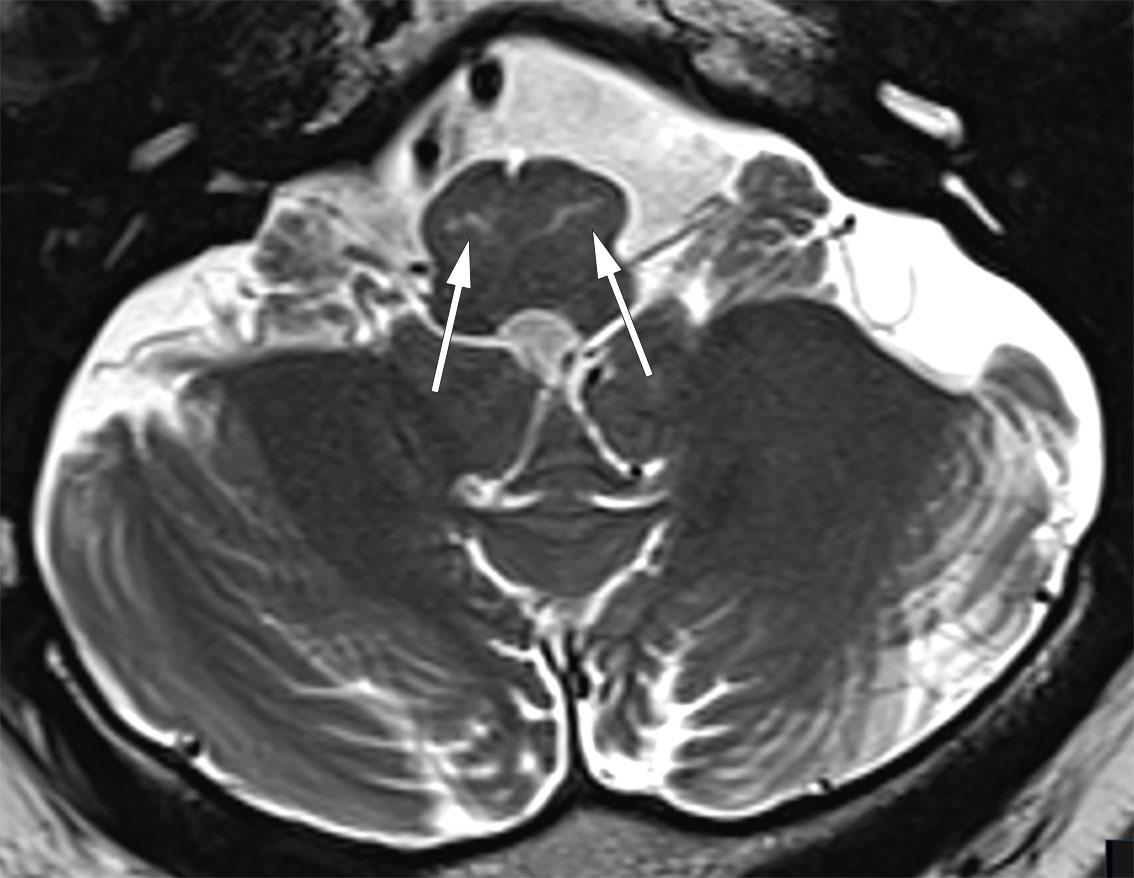

Videoen viser palatal tremor – en sjelden hyperkinetisk bevegelsesforstyrrelse som rammer den bløte ganen. MR-bildet av samme pasient viser T2-høysignal i nucleus olivaris inferior bilateralt, et radiologisk funn som samsvarer med det kliniske funnet, og som krever etiologisk avklaring.

En tidligere frisk mann i slutten av 50-årene ble henvist til nevrologisk vurdering på bakgrunn av tilfeldig funn ved cerebral MR som ledd i utredning av en ikke-relatert øyesykdom. MR-undersøkelsen viste T2-høysignal i hjernestammen svarende til nucleus olivaris inferior bilateralt uten kontrastopptak eller masseeffekt. Pasienten hadde ved undersøkelsen kontinuerlig palatal tremor, men ingen andre nevrologiske symptomer eller tegn.

Symptomatisk palatal tremor er hyppig assosiert med andre kliniske funn som tremor utenom ganen, okulær myokloni og ataksi. Dette skyldes affeksjon av Guillain-Mollarets triangel, et nevronnettverk som strekker seg mellom ipsilaterale nucleus olivaris inferior, nucleus ruber og kontralaterale nucleus dentatus. En triadeskade, oftest vaskulær, inflammatorisk eller neoplastisk, vil typisk gi disinhibisjon av nucleus olivaris inferior, enten uni- eller bilateralt, med såkalt hypertrofisk olivadegenerasjon som resultat. MR-undersøkelse kan da vise hypertrofi med økt T2-signal i området for nucleus olivaris inferior. Typisk tilkommer T2-høysignal i løpet av seks måneder etter skadetidspunktet, mens hypertrofien først oppstår etter ti til atten måneder. Hypertrofien vil avta over år, mens T2-høysignalområdene består (2).

Vår pasient hadde klinisk isolert palatal tremor. På MR var det tegn til stripeformet T2-høysignal i nucleus olivaris inferior bilateralt uten hypertrofi eller tegn til triangelskade. Ved kontroll femten måneder etter primærundersøkelsen var det uendrede MR-funn. Utredning med hensyn til nevroinflammatorisk eller revmatologisk tilstand var normal.